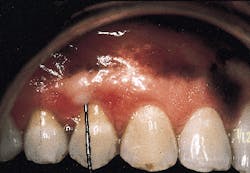

Photograph #5 was taken at the one-year postoperative visit. Probing depths around tooth #5 were reduced to 2 mm. Pocket closure was achieved and was maintained for a five-year observation period.

In principle, pocket closure in this case was obtained by regeneration of a new attachment apparatus.

Photograph #5: The area one year postoperatively. Probing depths are reduced to 2mm. In principle, pocket elimination has been effected by development of a new attachment apparatus.